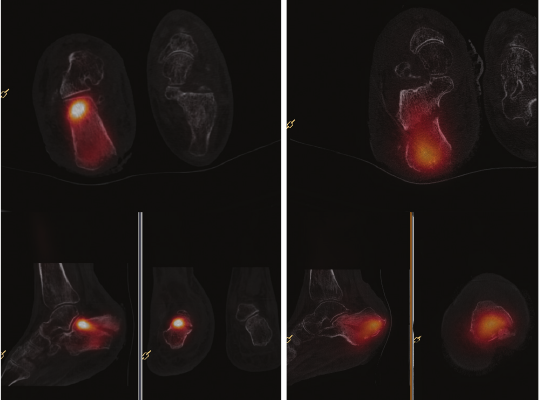

SPECT/CT can be performed, but in many cases the

need for simultaneous bone scanning can be avoided

by the CT fusion images. One such example is illustrated

in Figure 2. In this case, a single examination on the

BrightView XCT was able to rule out the important

diagnosis of osteomyelitis, conrm soft tissue infection,

and demonstrate an occult fracture as the source of pain

in this patient. And while it was not necessary in this

case, the combination of high quality anatomical images

with functional information can be invaluable for surgical

planning if such an intervention is required.

Figure 2 Tc-99m granuloscint SPECT/CT study of a 30-year-old female with persistent pain

two months following surgery for hallux valgus. The SPECT/CT study was performed on the

BrightView XCT to rule out osteomyelitis. White blood cell accumulation in the soft tissue

surrounding the head of the screw was observed, indicating a soft tissue infection. Some bone

resorption at proximal level of the screws, but no increased bone uptake and no interruption

of the bony cortex excluded osteomyelitis. Straight radiolucent line at metaphysic of

metatarsal bone marks the presence of a recent non-displaced transcortical fracture.

Clinical data courtesy of Universitair Ziekenhuis Brussel, Brussels, Belgium